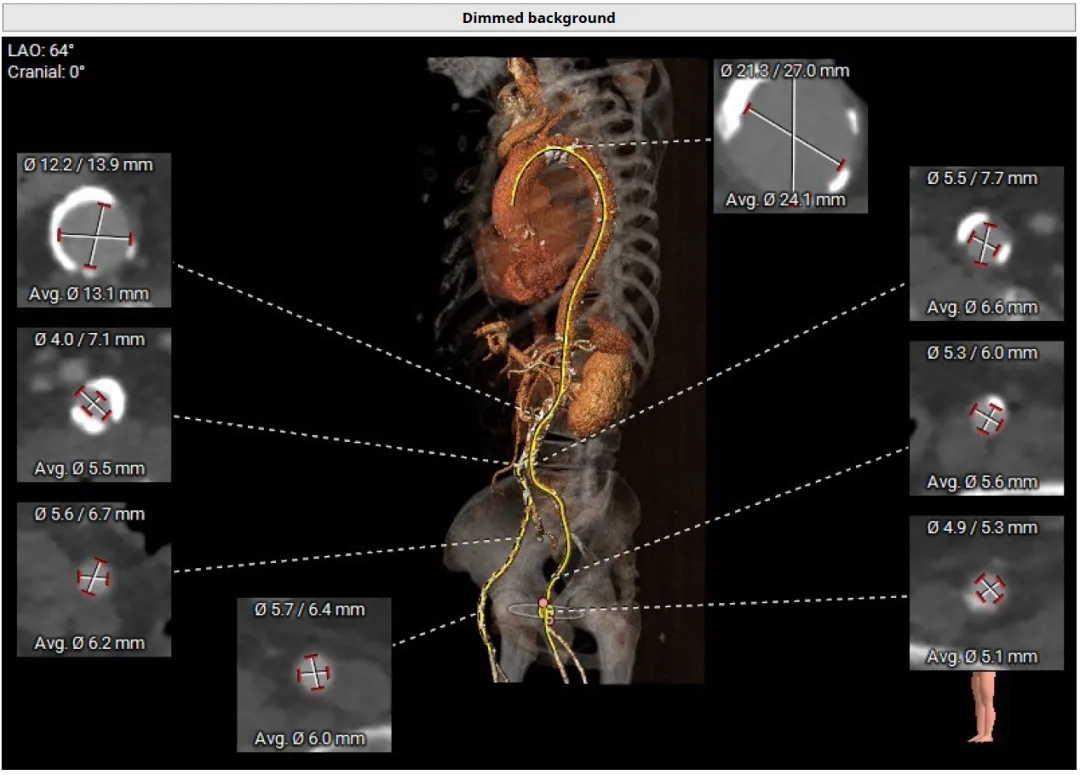

手术入路评估

手术入路方面,主动脉弓大弯侧弥漫性钙化,降主动脉粥样硬化伴钙化,右侧髂总动脉近环形钙化,内径稍小。左侧髂总动脉内径可,双侧髂外及股动脉内径可,右股动脉分叉位于股骨头平面下缘,左股动脉分叉均位于股骨头平面中下1/3。